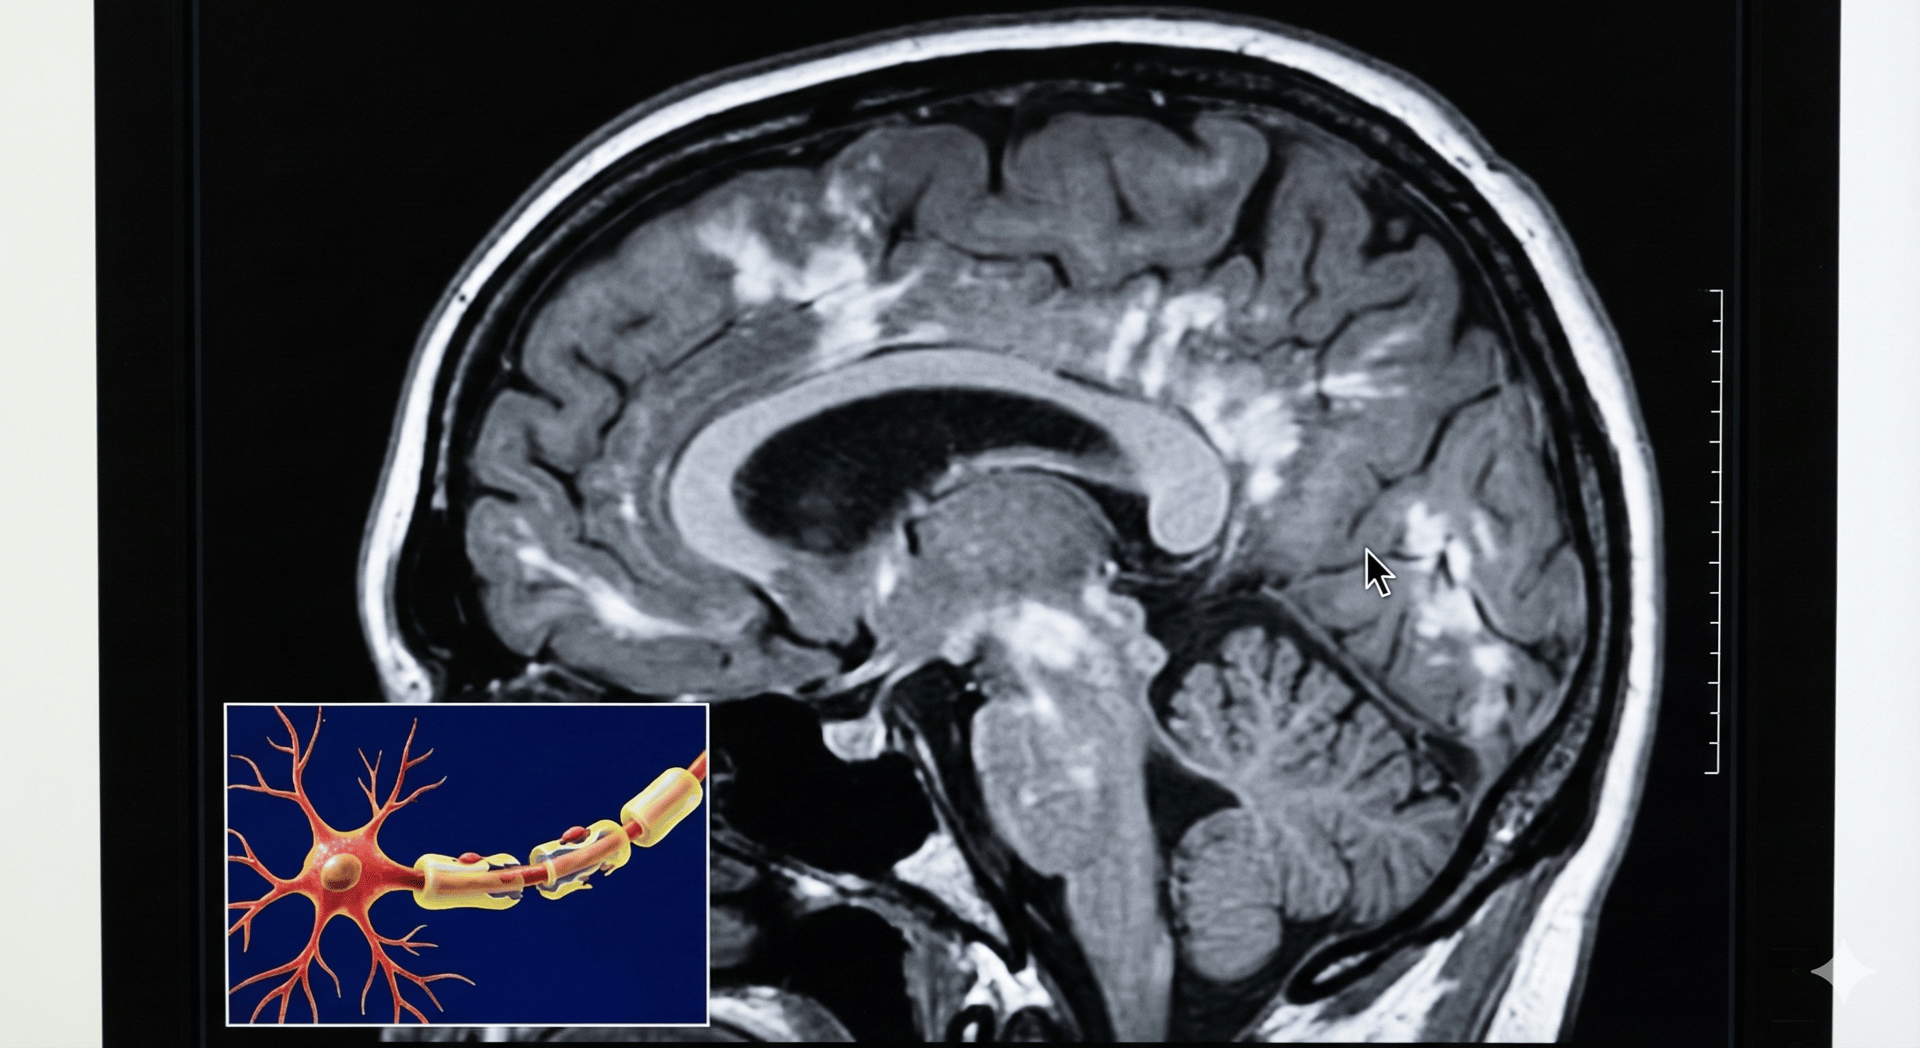

La esclerosis múltiple (EM) es una enfermedad del sistema nervioso central (cerebro, médula espinal y nervios ópticos) en la que participan procesos inmunológicos e inflamatorios que pueden afectar la mielina (cubierta protectora de las fibras nerviosas) y, en algunos casos, el propio tejido nervioso. Esto puede interferir con la transmisión de señales y manifestarse con síntomas neurológicos variables.

Resonancia magnética (MRI) para identificar lesiones compatibles en el sistema nervioso central.